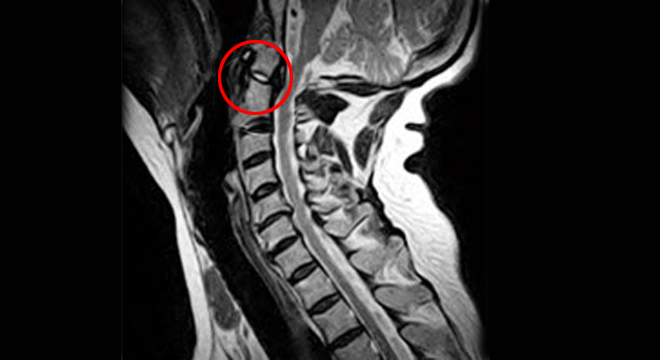

Schleudertrauma: Röntgenbild der Halswirbelsäule

• Röntgenuntersuchung der HWS, zum Ausschluss eines Knochenbruches

• Magnetresonanztomographie (MRT)